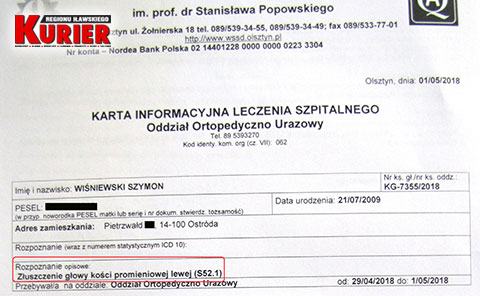

Ręka coraz bardziej puchła. 29 kwietnia matka zabrała 8-latka do szpitala w Nowym Mieście Lubawskim.

– Tu pan doktor, w odróżnieniu do lekarki w Iławie, zlecił wykonanie prześwietlenia jednej i drugiej ręki, dla porównania – opowiadała nam pani Karolina. – Gdy tylko zobaczył zdjęcie, od razu stwierdził złamanie łokcia z przemieszczeniem. Nie było już pytania, czy dziecko chce mieć założoną szynę czy nie. Od razu to zrobiono i skierowano nas do Olsztyna.

W nowomiejskim szpitalu od razu rozpoznano

złamanie łokcia z przemieszczeniem